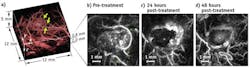

Photoacoustic images of a subcutaneous tumor treated with a therapeutic vascular disrupting agent were obtained both before and 24 and 48 hours after injection of the agent. Post-treatment images clearly show dynamic changes in the tumor vasculature due to the vascular shutdown that occurs over time, which results in strongly decreased perfusion particularly within the tumor core and thus reduced image contrast.

"The compelling in-vivo images provided by this novel photoacoustic sensing technology enable visualization of tumor-specific vascular features that cannot be observed noninvasively by existing imaging modalities to the depths reported in this study," says Paul Beard, head of the UCL photoacoustic imaging group. "This makes it a potentially powerful imaging tool for evaluating and developing new cancer treatments based on targeting tumor vasculature. Although our focus to date has been on demonstrating the technology as a preclinical research tool, there are a number of clinical skin-imaging applications that we plan to investigate, including diagnosis and treatment monitoring of skin cancers such as melanomas and characterizing abnormalities of the microcirculation associated with diabetes, venous disease, and inflammatory skin conditions such as dermatitis."